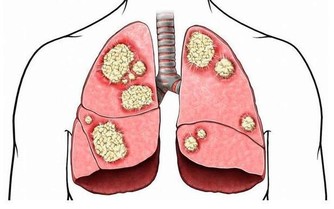

關節響可能是疾病徵兆

如果開始出現這樣的情況,一定要警惕,就可能是疾病的徵兆。

當人的年齡增大後,關節潤滑液會越來越少,潤滑度不夠,關節必定會出現磨損,這時候就會出現關節炎、骨刺、骨質疏鬆等疾病。

嚴重的甚至會導致骨關節壞死,這種屬於病理性關節響,一般伴隨著疼痛、活動受限,或者關節突然卡住。